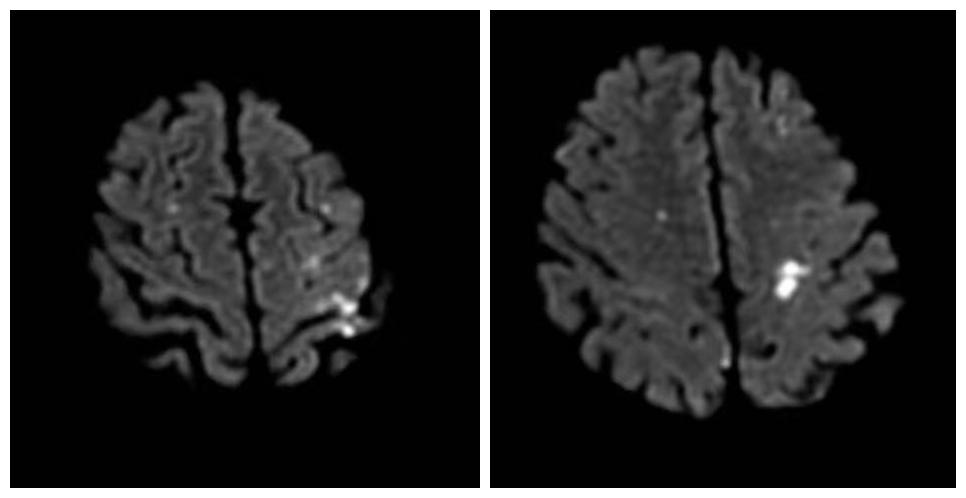

经过磁共振检查, 神经内科季新发主任 诊断:老人患有多发性脑梗死。进一步头颈部CTA检查,发现老人双侧椎动脉闭塞、颈动脉重度狭窄。

磁共振检查图:白色明亮处为脑梗处

多发性脑梗死是指脑部有两个以上的脑梗塞灶。如果堵塞的血管比较大,会导致大脑突然缺血,威胁病人的生命安全。